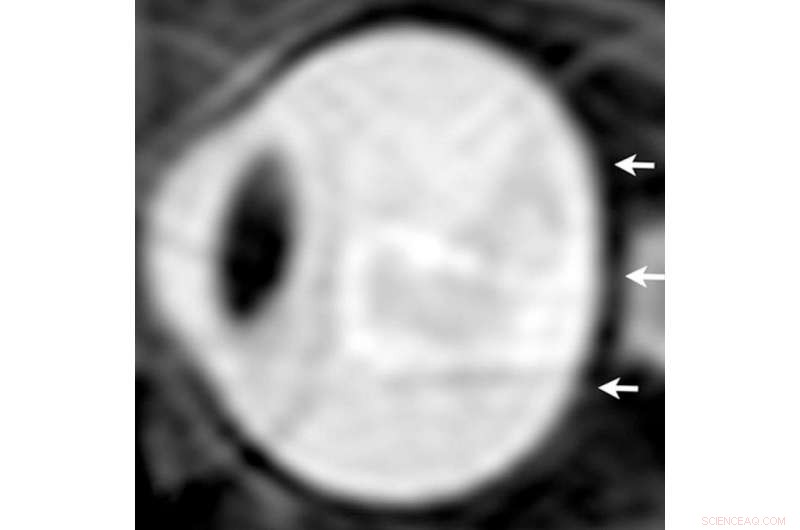

From a study of astronauts in 2012, sagittal oblique T2-weighted MR image of left eye after long-term exposure to microgravity. Note loss of convexity of the posterior scleral margin (arrows). Credit: Radiological Society of North America

The results showed that, compared to short-duration astronauts, long-duration astronauts had significantly increased post-flight flattening of their eyeballs and increased optic nerve protrusion. Long-duration astronauts also had significantly greater post-flight increases in orbital CSF volume, or the CSF around the optic nerves within the bony cavity of the skull that holds the eye, and ventricular CSF volume—volume in the cavities of the brain where CSF is produced. The large post-spaceflight ocular changes observed in ISS crew members were associated with greater increases in intraorbital and intracranial CSF volume.

"The research provides, for the first time, quantitative evidence obtained from short- and long-duration astronauts pointing to the primary and direct role of the CSF in the globe deformations seen in astronauts with visual impairment syndrome," Dr. Alperin said.